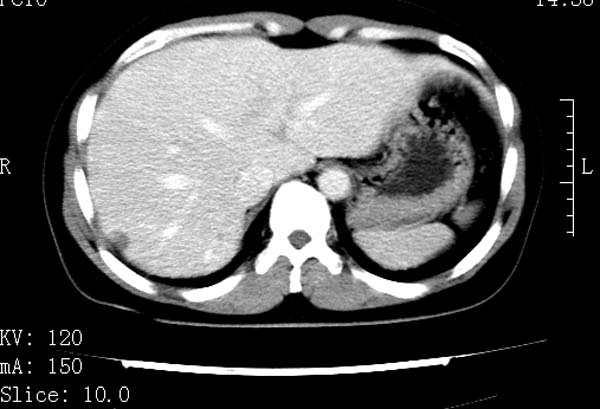

标题: CT22086:女44岁 肝右叶占位增强示巨大血管瘤,门脉期发现小 [打印本页]

标题: CT22086:女44岁 肝右叶占位增强示巨大血管瘤,门脉期发现小

请大家观察一下小灶   发表意见,谢谢

支持肝右叶血管瘤诊断。 小病灶亦考虑血管瘤改变。温习一下:

肝海绵状血管瘤ct平扫常呈均匀低密度,与邻近血管密度相仿。在脂肪肝背景下可呈相对高密度。在增强扫描时,一般早期(动脉期)呈周边结节状或弧形强化,其密度与同层面的血管密度相仿,随着时间延迟向中央渐进性充填,注药后5~7分钟,逐渐扩大至全瘤强化,强化密度逐渐降至稍高于或等于正常肝脏。大的血管瘤往往中央有星形、大的低密度区,可以为纤维化或囊性变所致,纤维化成分可在延迟2 o分钟时完全充填,呈等密度,但囊变区则不会强化。不典型ct表现常见于≤3 cm的小血管瘤。小的血管瘤可以在动脉期即呈全部致密的均匀强化,不呈典型的周边结节状强化表现,但其密度往往较高,与主动脉相仿,在延迟期呈高或等密度。其他不典型的ct表现有:增强扫描强化不明显,呈点状较轻程度的强化,充填慢,可能与供血动脉较细和较大的血管间隙有关以及中央先强化等。

延迟扫描三个病灶都呈等密度改变。肝多发血管瘤,较典型。